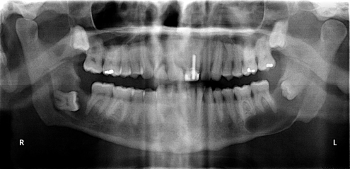

Ficam convidados todos os colegas a trazerem casos clínicos fotografados ou em radiografias (num ficheiro que possibilite a sua projeção), cujos diagnósticos e indicações cirúrgicas possam ser discutidos por todos.

Fotos de casos clínicos